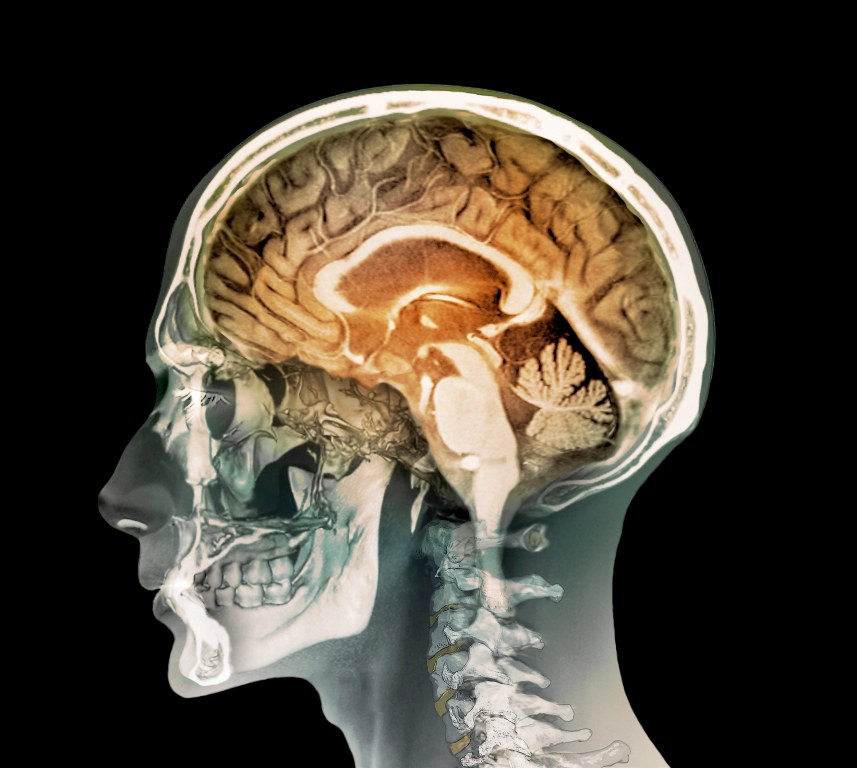

Анатомия мозга: Рентгеновские снимки для презентаций